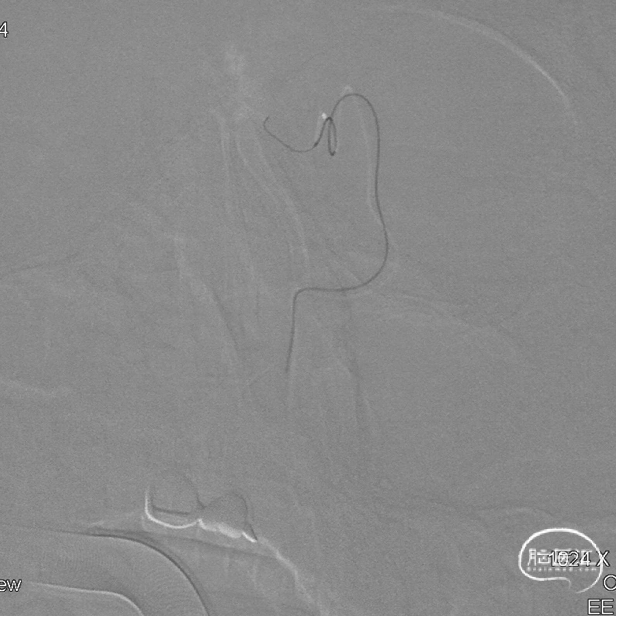

Marathon微导管在Hybrid0.007微导丝导引下经左侧眼动脉超选至左侧筛前动脉,接近瘘口。

通过Marathon微导管超选造影,显示微导管楔入到靠近瘘口的动脉端。